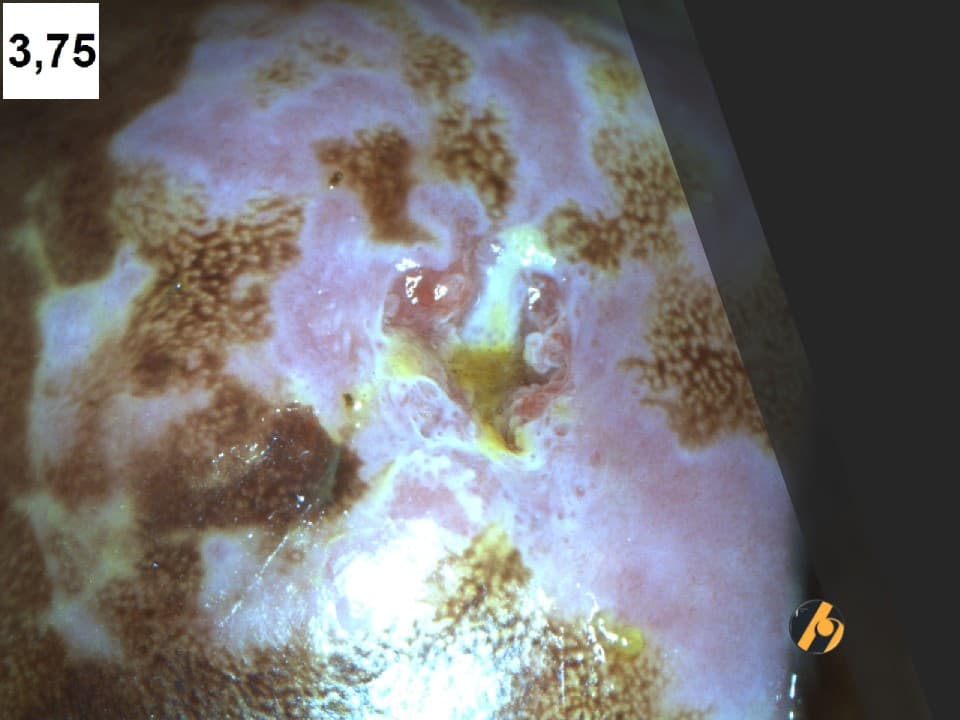

Mozaik je kolposkopska slika koja označuje žarišno prisustvo svijetlih poligonalnih polja međusobno odvojenih tankim crvenim linijama, koja nastaje guranjem klinova i šapica atipičnog epitela u dublje slojeve cervikalne strome, pri čemu stromalne papile s krvnim žilama dopiru do površine epitela. U slučaju mozaika arborizacija krvnih žila teče u horizontalnom pravcu, tako da su kapilari paralelni s epitelnom površinom na kojoj ostavljaju dojam odvojenih polja epitela koja čine sliku mozaika. Interkapilarna distanca, promjer kapilara, veličina i pravilnost mozaičnih polja omogućuju razlikovanje nježnog od grubog mozaika, iza kojih se kriju metaplastični epitel ili skvamozna intraepitelna lezija.